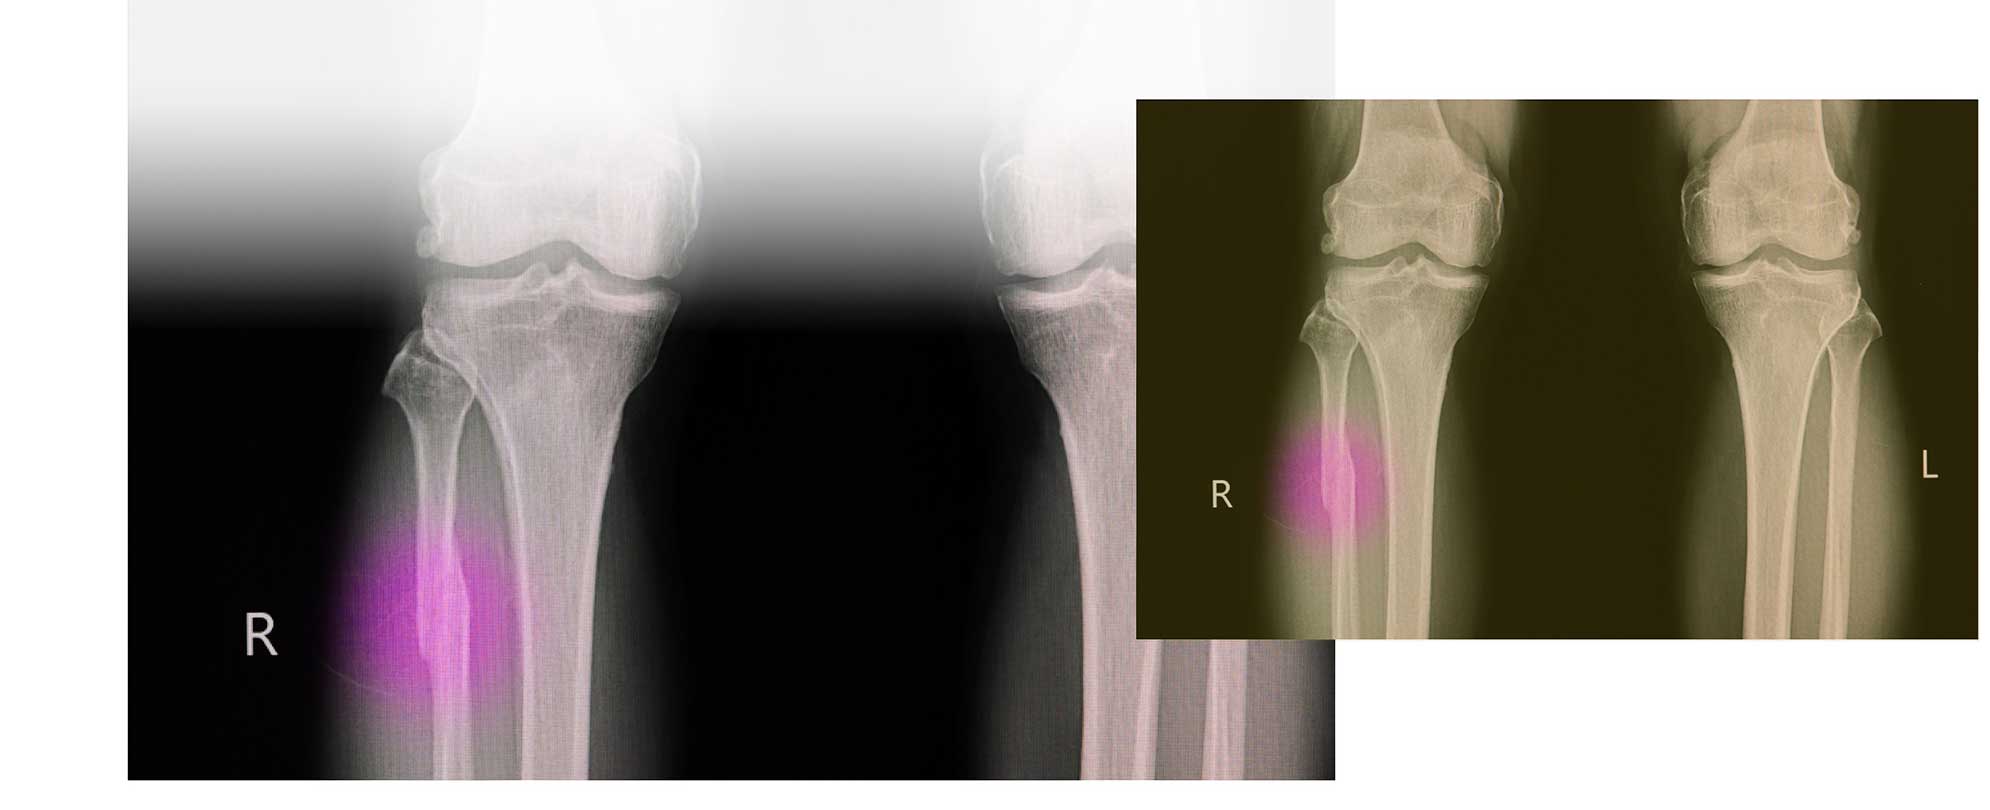

Stress fractures are micro cracks in the bone that only affect the surface (initially).

It is important to diagnose it properly because these micro cracks can become a complete fracture. How do they manifest themselves? Normally you will feel progressive muscle pain, stiffness and bone pain in the affected area.

If this is the case, it is recommended that you stop training and consult your family doctor or physiotherapist. They will be able to assess whether there are stress fractures on x-rays or other techniques, because not all stress fractures show up on x-rays. Since 2016 physiotherapists have been able to refer directly to specialists for x-rays if they deem them necessary, while keeping the family physician informed. Following the assessment, if there is a stress fracture, you will need to stop training to allow your body to complete the healing process.